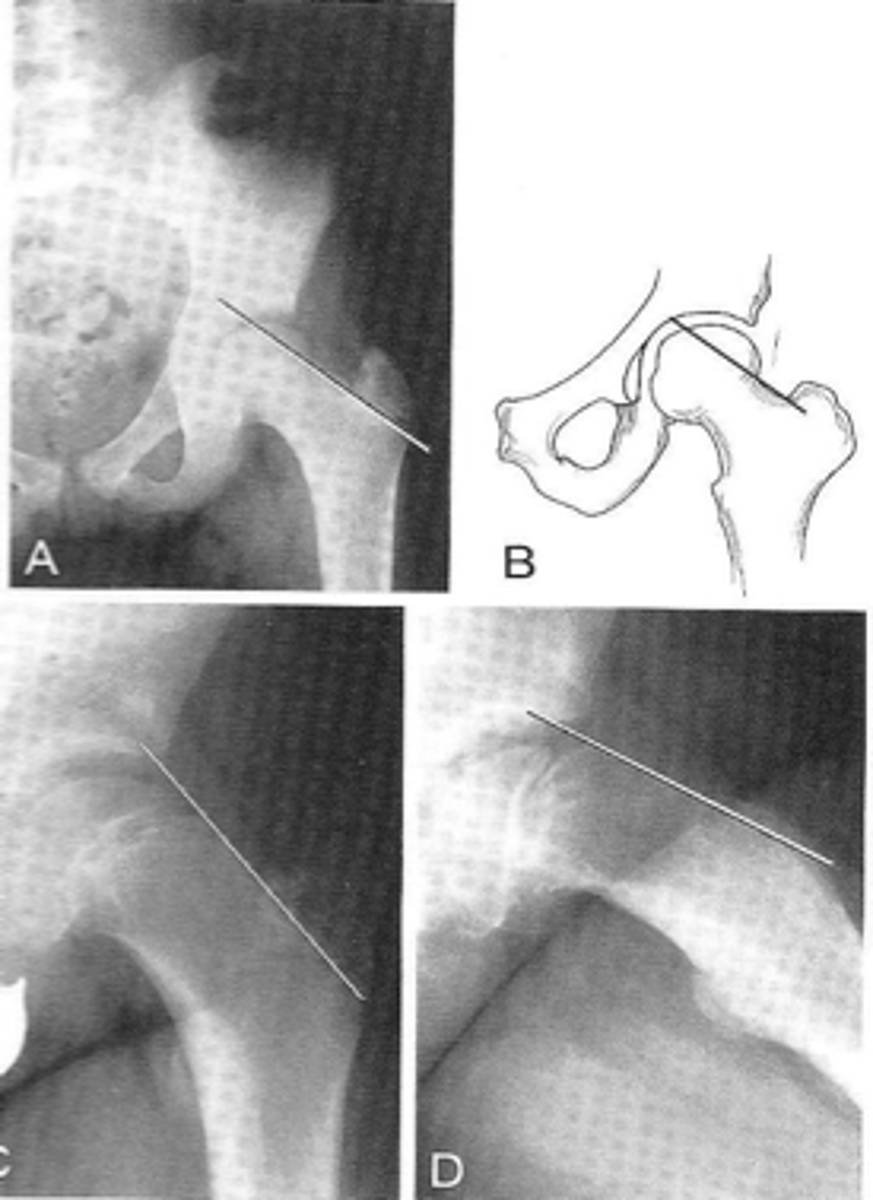

8

New cards

Left anterior sacroiliac joint

ID 4 (joint)

<p>ID 4 (joint)</p>

9